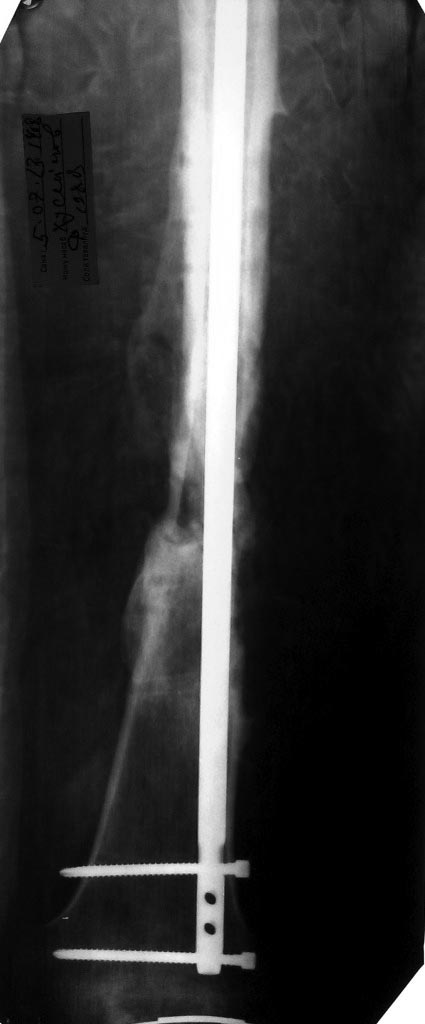

Молодой парень, 25лет. Травму получил в ноябре 2012 года, ДТП.Оперирован в сельской больнице, остеосинтез перелома бедренной кости пластиной и АВФ на голень с этой стороны, наложена гипсовая повязка коксит на 3 месяца. В момент госпитализации разгибательная контрактура коленного сустава (движения в коленном суставе сгибание 10 градусов) 02.07.2013 произведена операция - удаление металоконструкции с бедренной кости, костная аутопластика( из подвздошной кости) и БИОС бедренной кости универсальным гвоздем ChM. ЭОПа у нас нет, пользуемся переносным рентгенапаратом. Как быть с ложным суставом голени?

1. БИОС голени- оптимальный вариант,но при отсутствии желаемого сгибания в коленном суставе сможем ли мы сделать( Наш опыт - всего 30 операций по БИОСу)

2ЧКДО по Илизарову( после АВФ)

Снимки во вложении.За качество снимков заранее извиняюсь.